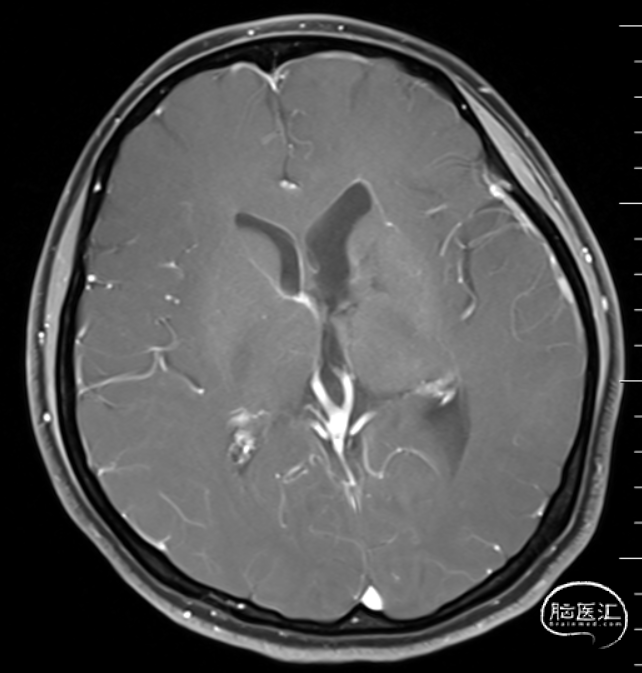

头部磁共振提示:左侧侧脑占位病变,增强后不染色